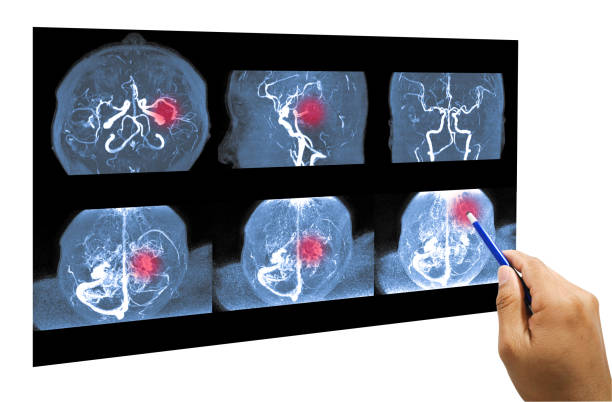

뇌졸중 증상

모야모야병의 가장 일반적인 증상 중 하나입니다. 뇌졸중 증상은 언어 장애, 인지 장애(기억력 감퇴, 학습 장애 등), 시각 장애(시야 손실, 양안 시력 장애), 운동 장애(양쪽 다리나 팔의 약화, 불균형, 혹은 어색한 움직임 등) 등이 있습니다.

반복성 뇌졸중

모야모야병은 뇌졸중 발생 위험이 높습니다. 반복적인 뇌졸중은 뇌조직 손상, 체력 저하, 기능 손상 등을 초래할 수 있습니다.